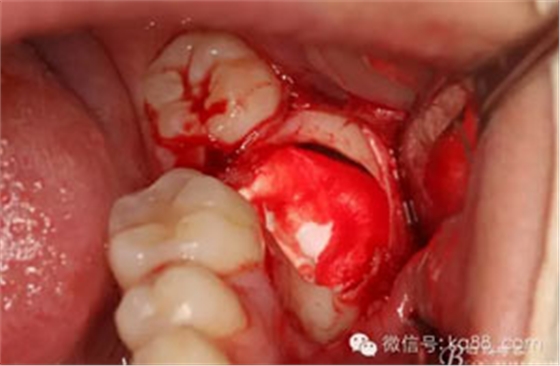

圖13.縱分牙冠

圖14.分開近遠(yuǎn)中牙冠及牙根及周圍囊壁。

圖15.37拔除后的牙槽窩情況